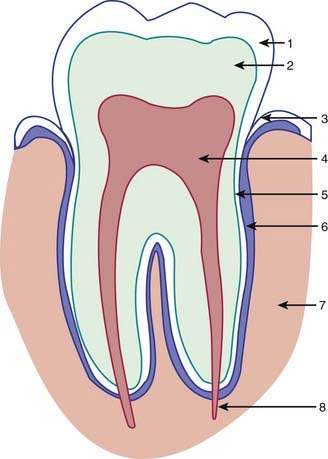

Left untreated, dental caries usually destroy most of the tooth and invade the dental pulp (Fig. 304-3), leading to an inflammation of the pulp (pulpitis) and significant pain. Pulpitis can progress to pulp necrosis, with bacterial invasion of the alveolar bone causing a dental abscess (Fig. 304-4). Infection of a primary tooth can disrupt normal development of the successor permanent tooth. In some cases this process leads to sepsis and infection of the facial space.

Figure 304-3 Basic dental anatomy: 1, enamel; 2, dentin; 3, gingival margin; 4, pulp; 5, cementum; 6, periodontal ligament; 7, alveolar bone; 8, neurovascular bundle.